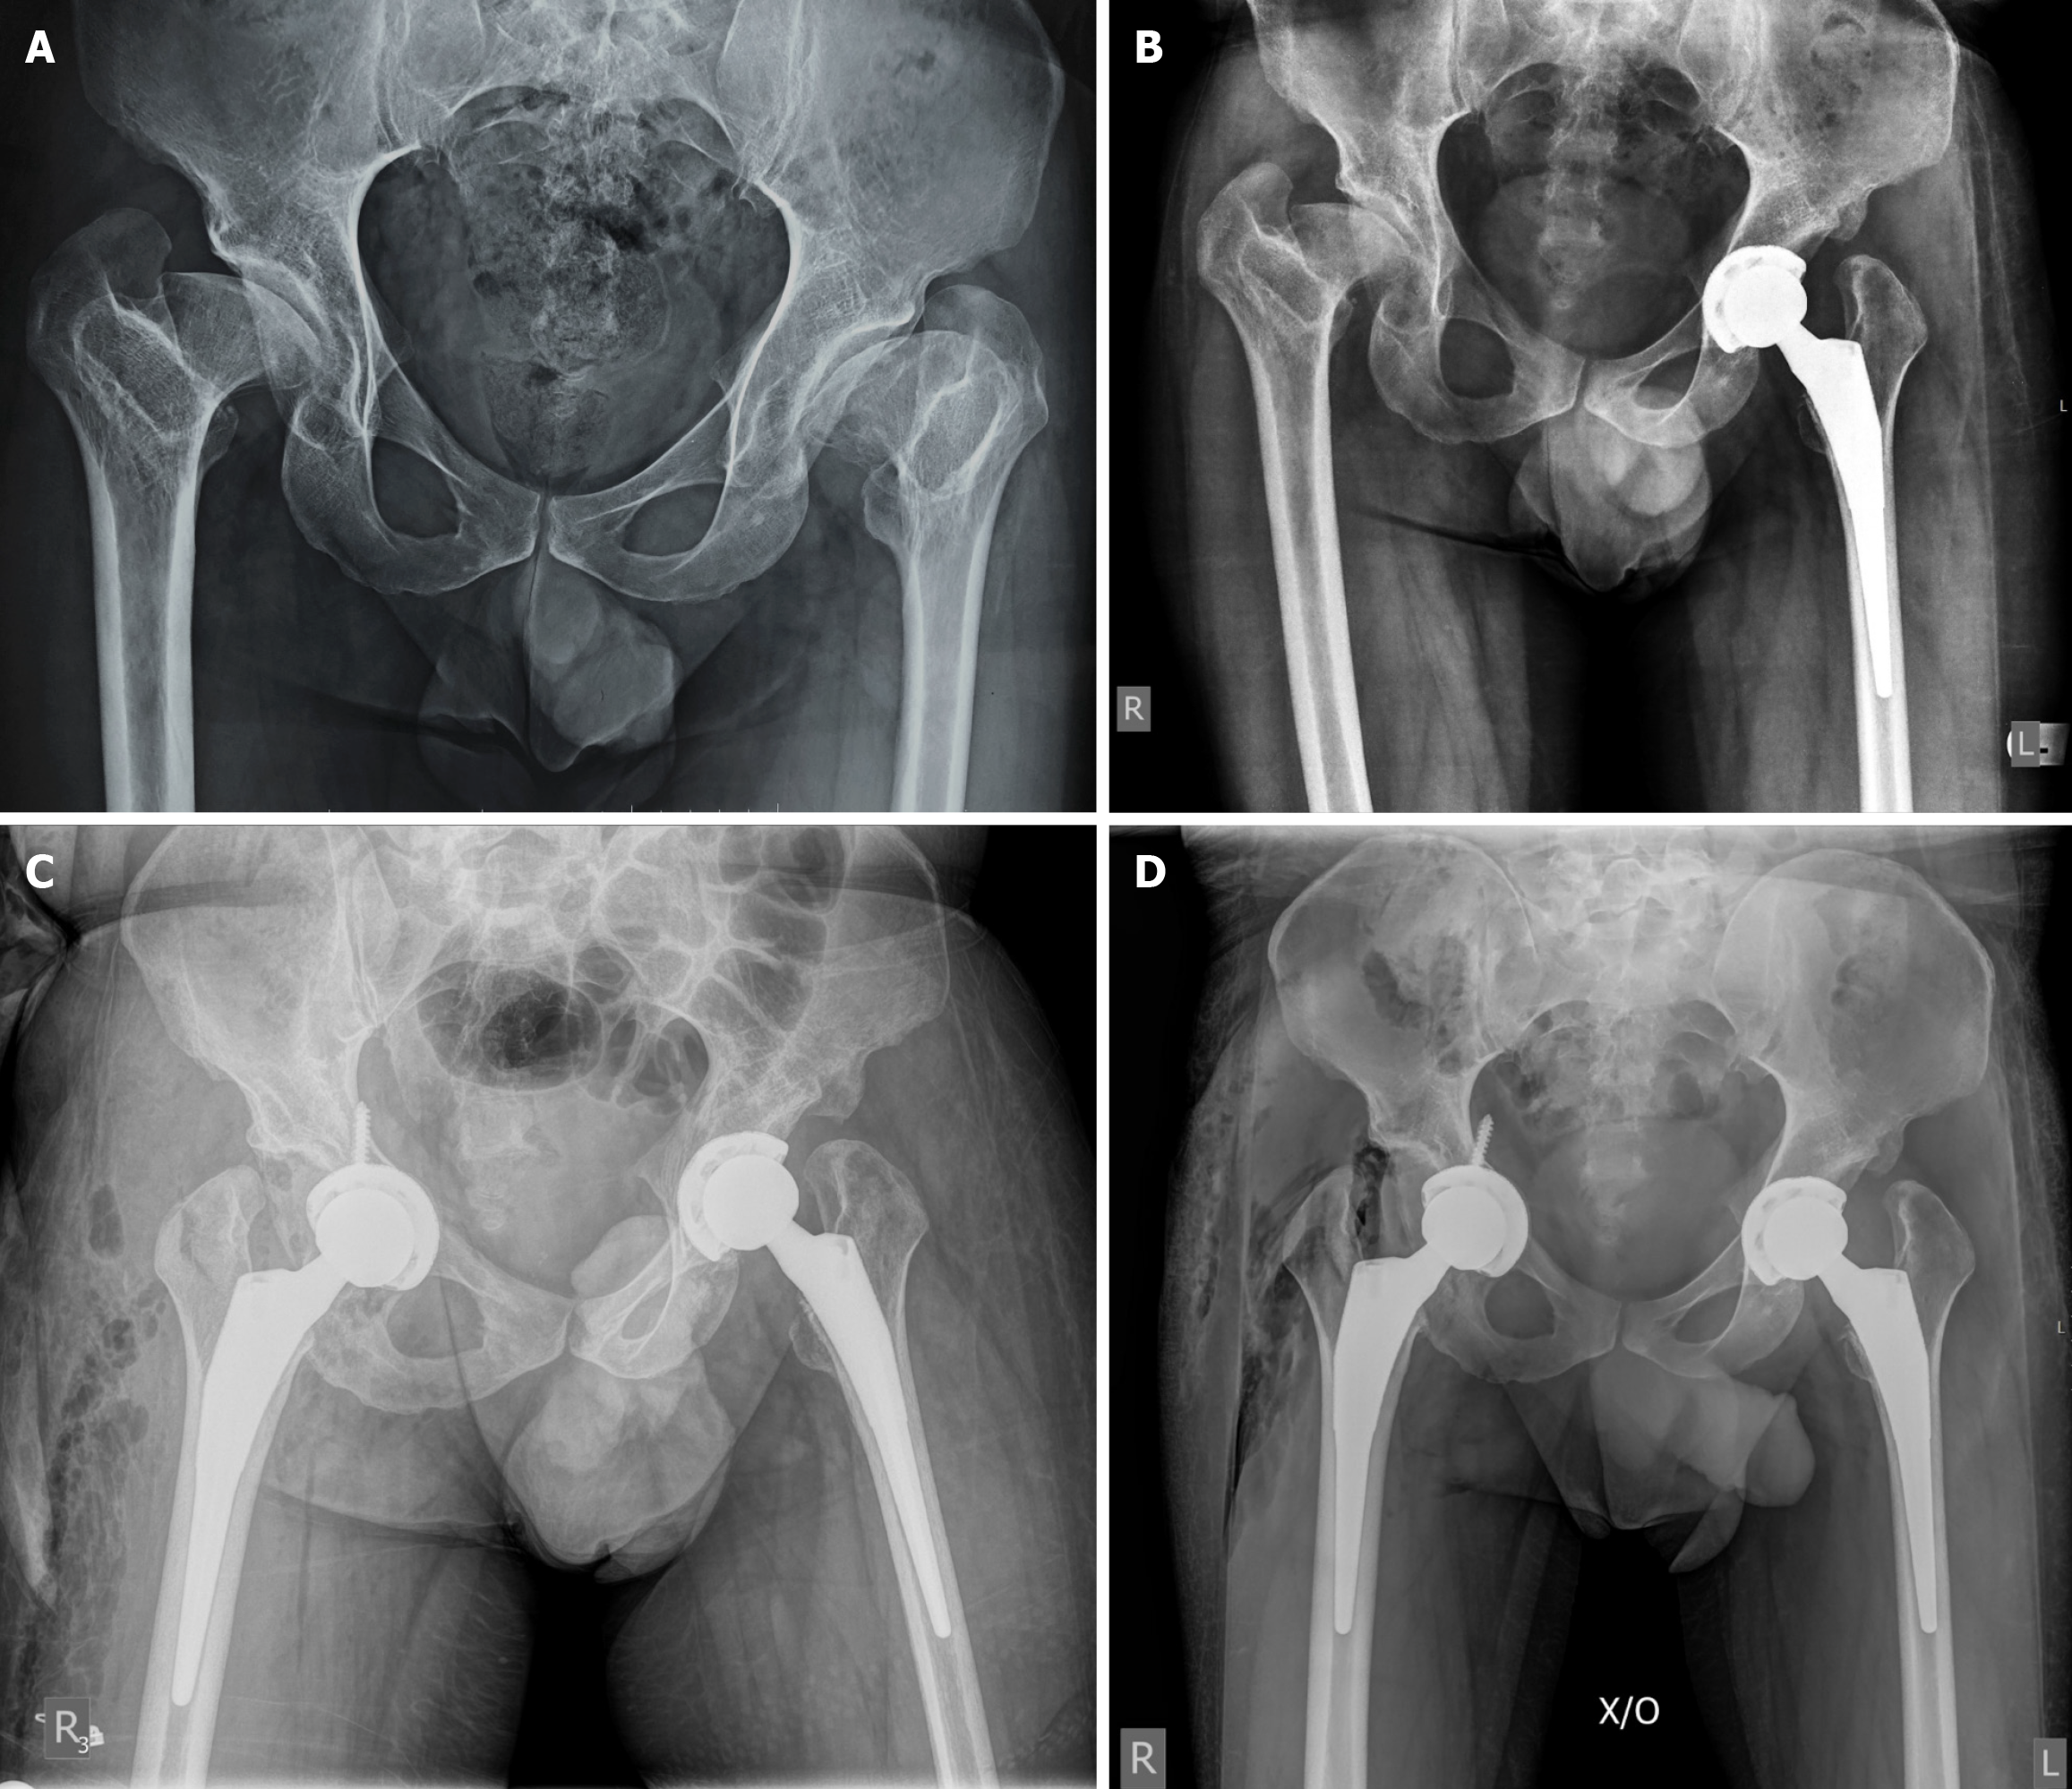

Figure 3 Postoperative and long-term radiographic follow-up after acetabular screw trimming.

A: Immediate postoperative anteroposterior pelvic radiograph showing the trimmed acetabular screw. No implant was revised; B: Anteroposterior pelvic X-ray at 3 years after surgery. No implant migration or loosening is apparent.